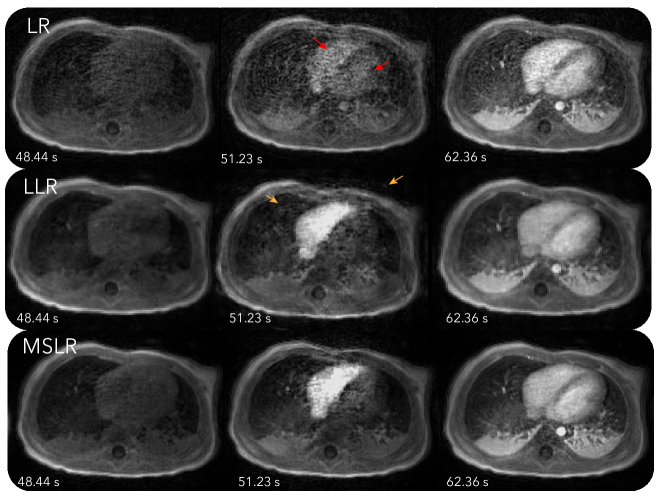

Figure 2 and Video S2S3, and S4 show reconstruction results with LR, LLR and MSLR. As pointed by the red arrows, reconstruction with LR shows unrealistic dynamics, with contrast enhancing in both left and right ventricles at the same time. The other reconstructions show contrast enhancing first in the right ventricle then the left ventricle, which is physiologically correct. On the other hand, LLR displays more flickering temporal artifacts, which can be seen more visibly from Video S3. These artifacts are also pointed out by the orange arrows in figure. MSLR achieves a balance between representing contrast enhancement dynamics and reducing artifacts.

Refer to caption

Figure 2: Reconstructions with LR, LLR and MSLR on the first DCE dataset. Dynamics can be seen more clearly in Video S2, S3, and S4. As pointed by the red arrows, reconstruction with LR shows unrealistic dynamics, with contrast enhancing in both left and right ventricles at the same time. The other reconstructions show contrast enhancing first in the right ventricle then the left ventricle, which is physiologically correct. On the other hand, LLR displays more flickering temporal artifacts, which can be seen more visibly from Video S3. These artifacts are also pointed out by the orange arrows in figure. MSLR achieves a balance between representing contrast enhancement dynamics and reducing artifacts.

In Figure 2, we compared the effect of different LR modelings. Consistent with observations in [34, 5], LR has difficulty representing spatially localized dynamics, and exhibits temporal blurring of contrast enhancements in the ventricles. LLR is able to depict spatially localized dynamics well and show distinct contrast enhancements in the left and right ventricles. However, compared to MSLR, LLR has more spurious temporal artifacts. Because LR and LLR are subsets of MSLR, MSLR in principle can always perform better with the suitably tuned regularization parameters. The purpose of the experiment is to show that with a fixed regularization relationship between scales described in Equation (6), MSLR can still represent dynamics with the appropriate scale. This is also supported qualitatively in the MSLR decomposition shown in Figure 3.